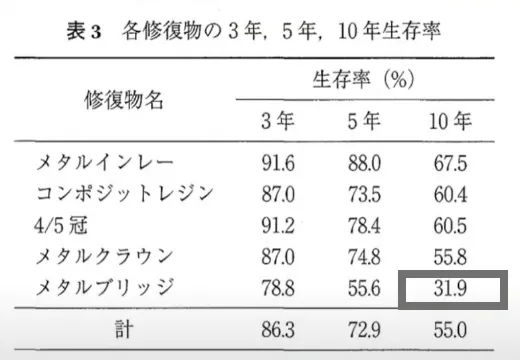

保険適用のブリッジと比較しても、3倍の確率で長持ちします。

保険適用のブリッジが

10年後も使える確率は31.9%

引用元:https://www.jstage.jst.go.jp/article/jdh/58/1/58_KJ00004846513/_pdf